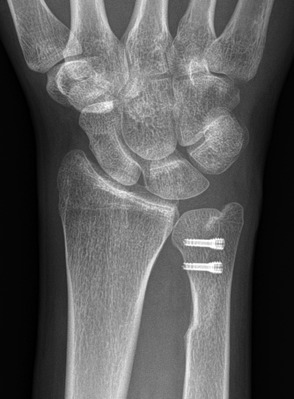

Figs. 4-A, 4-B, and 4-C Case illustration of the ulnar sliding osteotomy.

Fig. 4-A.

Preoperative appearance.

Fig. 4-B.

Six weeks postoperatively.

Fig. 4-C.

Twelve weeks postoperatively.

Use fluoroscopy to check the result (Figs. 4-A, 4-B, and 4-C).